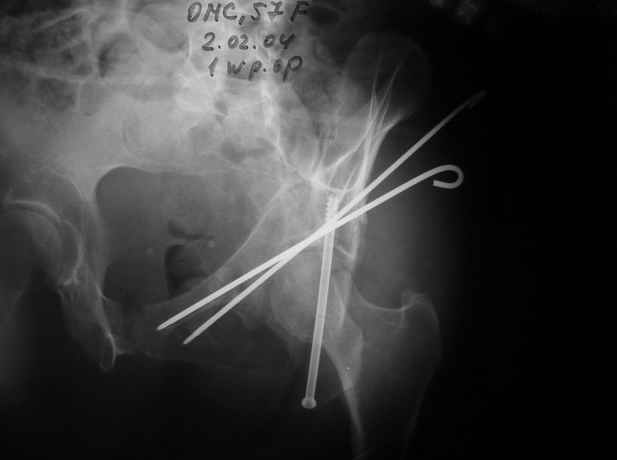

Женя! Класный перелом. Отлично репонируется изнутри таза, но лучше фиксированть сзади. Классический перелом для двустороннего доступа.

Однако есть альтернатива. Репозиция из подвздошного доступа тазовыми щипцами с разнодлинными браншами или тазовым пистолетом, а фиксация задней колонны через седалищный бугор или тазрвыми винтами 4,5 или каннюлированными 6,5 или 7,3. По-моему я посылал на ортофорум такой снимок, когда жаловался на ишемический неврит седалищного нерва через сутки после операции. Не забудь про шейку бедра - мне кажется будет хорош длинный PFN любой фирмы, какую ты найдешь, а нет так UFN + miss a nail, как это здорово делают мои земляки - Ебурбуки. Пока.

02.02.04